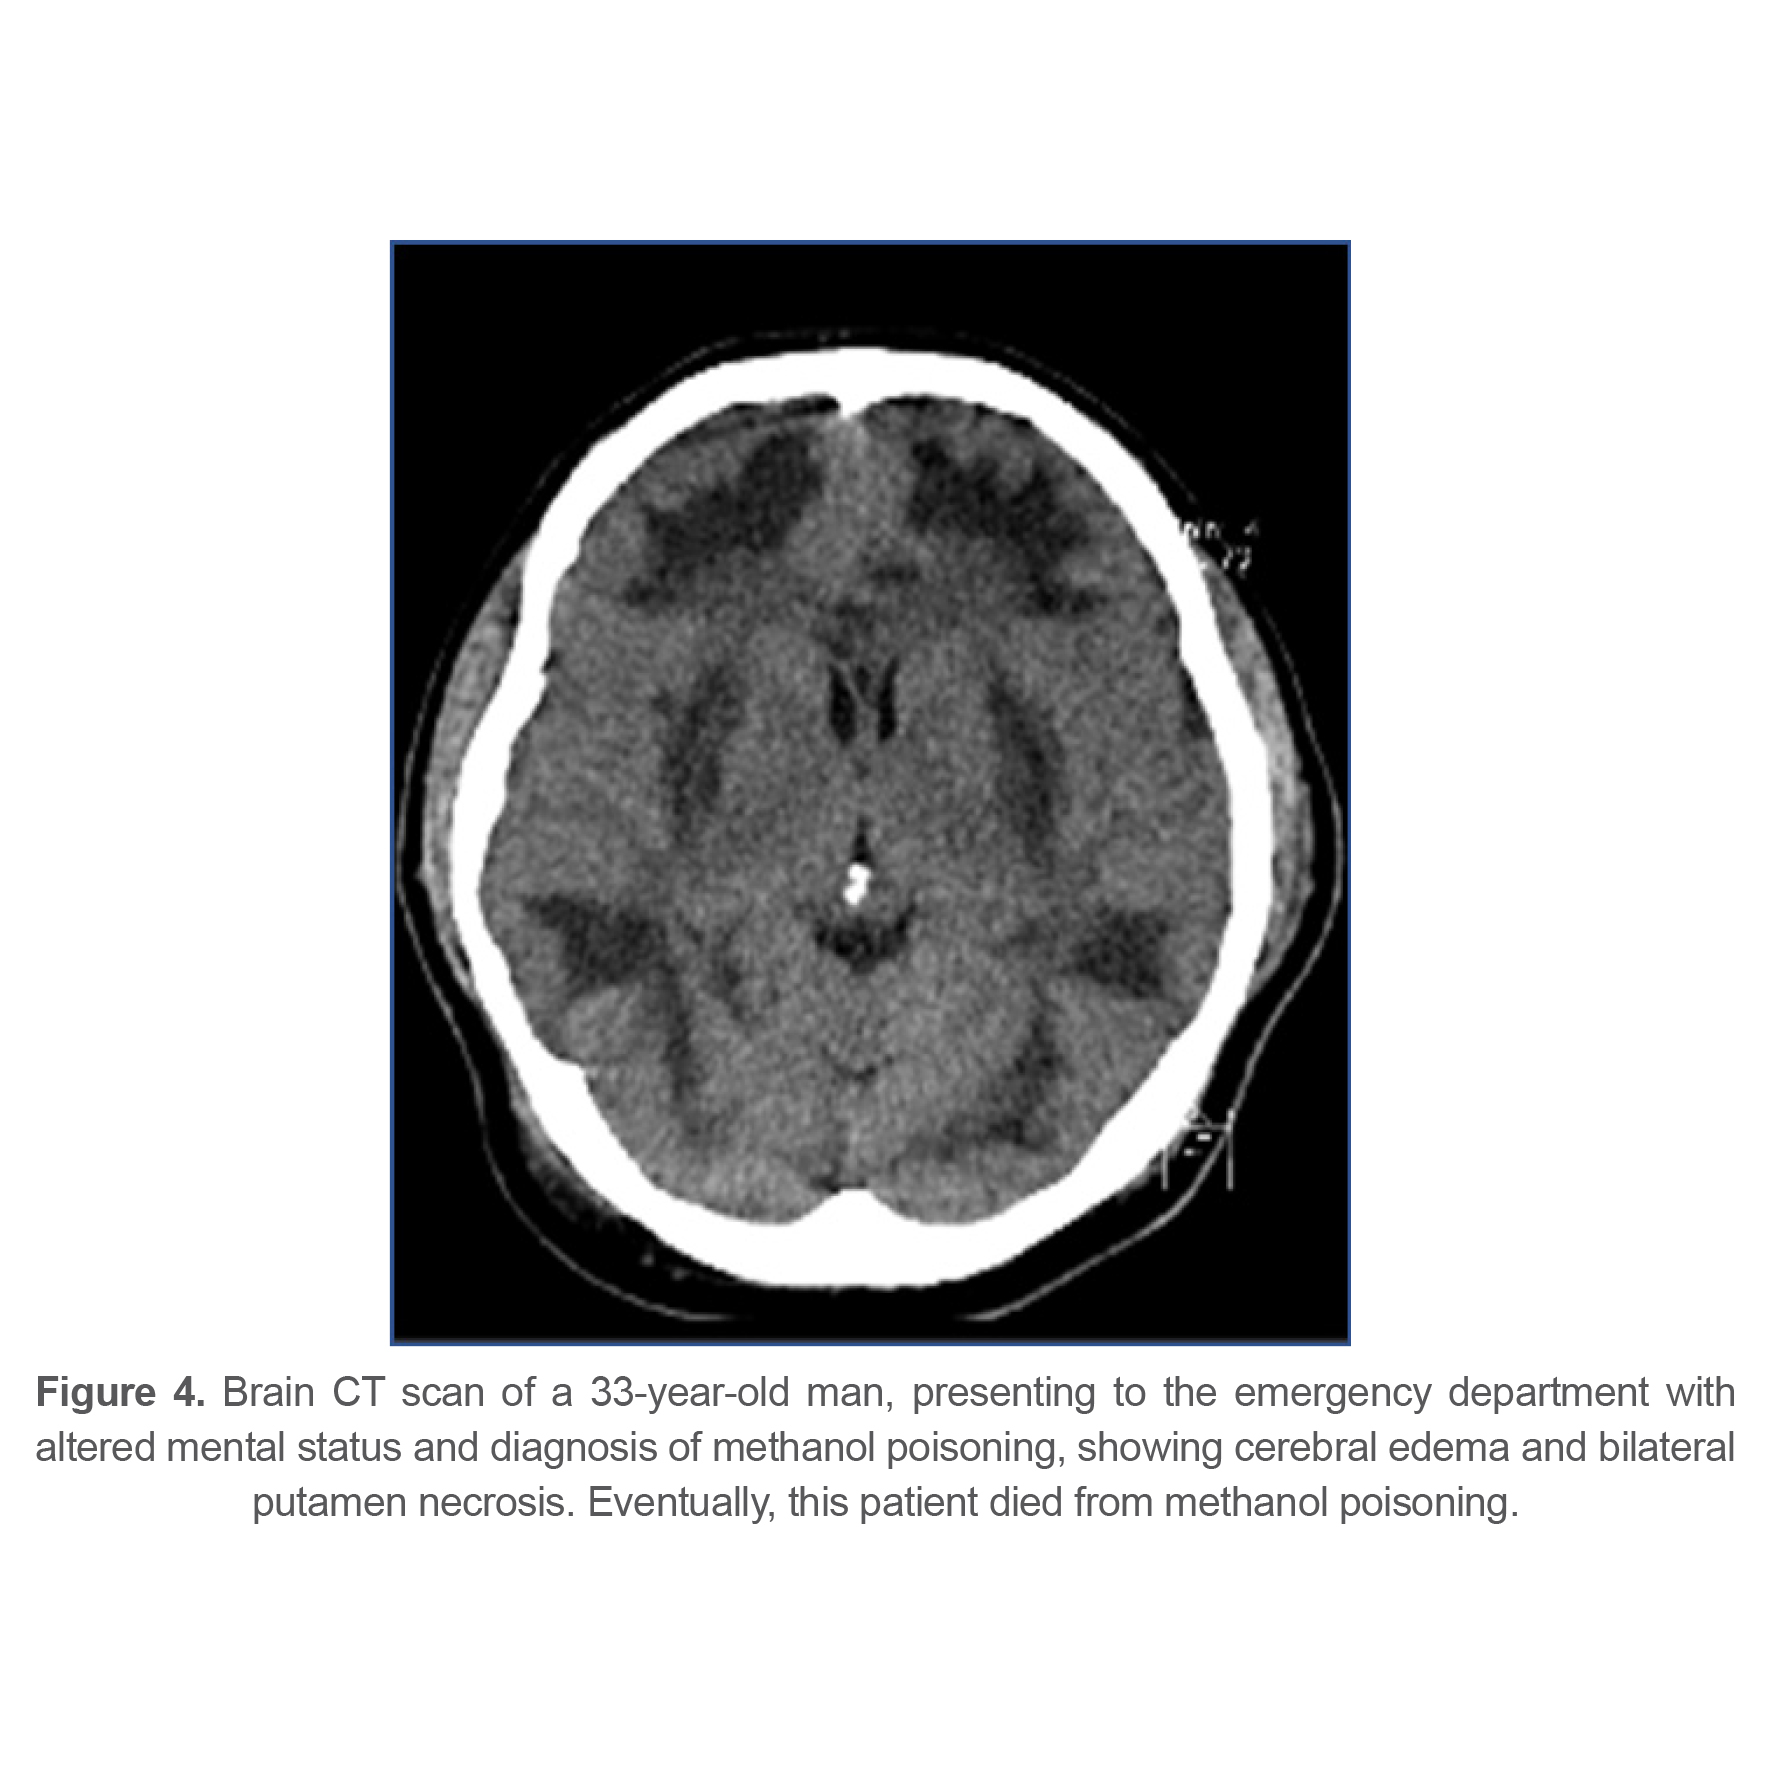

At last, 143 patients (77.72%) recovered completely, 27 patients (14.67%) had sequels at time of discharge from hospital and 14 patients (7.61%) died from methanol poisoning. Different types of complications and their frequency are listed in table 3. 21 patients (11.4%) had some sort of ophthalmologic complications at the time of discharge indicating that ophthalmologic complications were the most common complication among survivors. Figures 1-4 show brain CT scan of 4 patients with brain complications.

Figure 4. Brain CT scan of a 33-year-old man, presenting to the emergency department with altered mental status and diagnosis of methanol poisoning, showing cerebral edema and bilateral putamen necrosis. Eventually, this patient died from methanol poisoning.